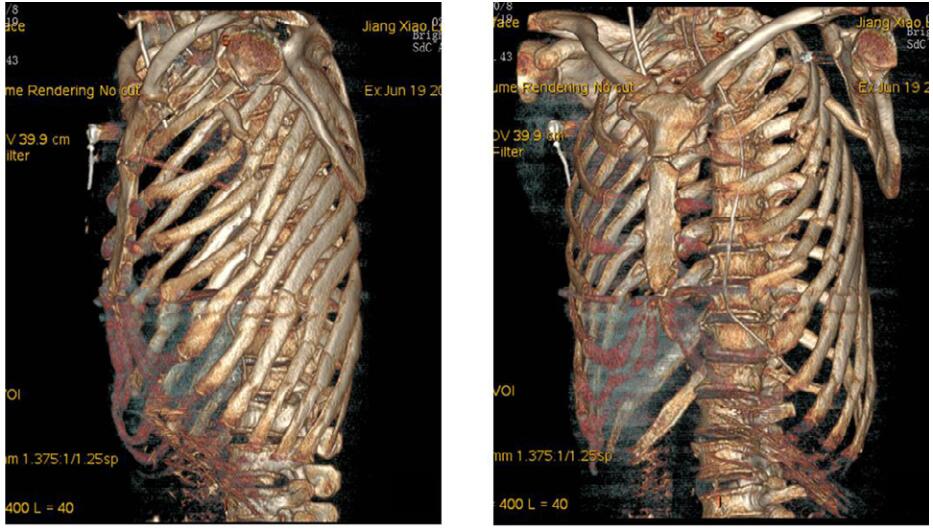

术后返回EICU,患者生命体征逐渐平稳,血管活性药物剂量逐步下调,复查CT及三维重建未见新发血肿,见图 3。1周后脱机拔管,10 d后拔除胸引管,2周后转出监护室。术后停用镇静镇痛药物后即发现患者存在腋神经、臂丛神经损伤迹象,后转至骨科行肌电图,提示臂丛神经上、中、下三支均严重受损,后期行康复治疗。

| 图 3 术后复查胸部CT及三维重建 |

创伤性腋动脉破裂出血是一种临床少见、致死率高的肩部损伤,临床上发生率极低。腋动脉自身的创伤性损伤仅为主动脉损伤的2.9%~9%[1]。腋动脉损伤常常继发于上肢关节脱位,与下肢相比,其发生率不足1%[2]。因腋动脉位置隐匿,临床表现无明显特异性,易引起忽视。Kelley等[3]认为,当患者存在肩关节外伤史,动脉彩色多普勒超声检查发现存在动脉血流变化以及不断增大的腋窝肿块即可及时诊断腋动脉损伤。本病例血管造影可见左侧腋动脉起始部造影剂外渗,在置入覆膜支架后腋动脉显影通畅,无造影剂外溢现象,术后行三维重建可见支架影。